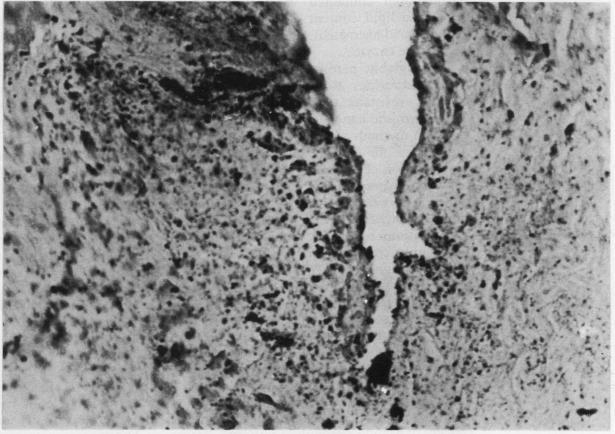

Macroscopic evidence of bruising from human bite marks may be inconclusive and routine histochemical methods of showing extravasated erythrocytes can be unreliable. Leuco patent blue staining, for the presence of peroxidase, Amido black B, a tinctorial staining method for haemoglobin, Perls's reaction for ferric iron (haemosiderin), Masson-Fontana for melanin, Masson's trichrome, a connective tissue strain, and the benzidine reaction for haemoglobin peroxidase were carried out in three forensic cases and one experimental case. A modified benzidine method was the most reliable indicator of haemoglobin activity, especially where dispersion into extra-cellular tissues had occurred. The resilience of the erythrocyte peroxidase enzyme to temperature changes and fixation supports the concept of a "pseudo-peroxidase" in those cells. It is concluded that free haemoglobin from bite marks, or indeed other forms of blunt trauma, may best be shown by the benzidine reaction and that exemption certificates for use of this prohibited substance may be worth pursuing.

人类咬痕造成的瘀伤的宏观证据可能不明确,而显示红细胞外渗的常规组织化学方法可能不可靠。在三个法医案例和一个实验案例中,进行了用于检测过氧化物酶的无色专利蓝染色、用于检测血红蛋白的氨基黑B(一种染色方法)、用于检测三价铁(含铁血黄素)的佩尔斯反应、用于检测黑色素的马森-丰塔纳染色、用于检测结缔组织的马森三色染色以及用于检测血红蛋白过氧化物酶的联苯胺反应。改良的联苯胺方法是血红蛋白活性最可靠的指标,尤其是在血红蛋白已扩散到细胞外组织的情况下。红细胞过氧化物酶对温度变化和固定的耐受性支持了这些细胞中存在“假过氧化物酶”的概念。结论是,咬痕或其他形式钝器伤中的游离血红蛋白,最好通过联苯胺反应来显示,并且可能值得申请使用这种违禁物质的豁免证书。